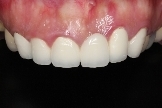

病患治療後,最終假牙完成照。

病患恢復自信的笑容。